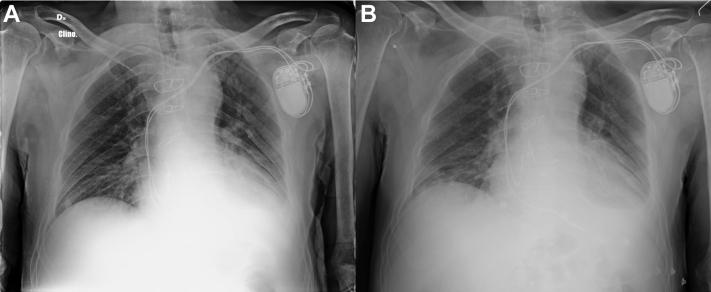

Syncope as the presenting symptom of COVID-19 infection.

HeartRhythm Case Rep. 2020 May 5;6(7):363-366. doi: 10.1016/j.hrcr.2020.04.015. eCollection 2020 Jul.

Syncope as the presenting symptom of COVID-19 infection.晕厥作为新型冠状病毒肺炎感染的首发症状